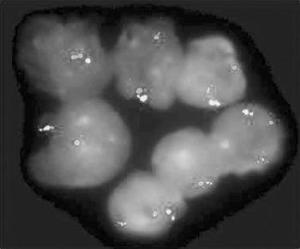

胸部肿瘤内科 | 精准靶向治疗成功救治罕见基因突变肺癌患者黄韵坚主任医师团队通过基因检测,在EGFR/ALK等常见靶点全阴性的绝境中,RNA测序揪出仅占肺癌1%的罕见“钻石靶点”NTRK融合突变,为治疗打开生命通道。团队立即启用NTRK抑制剂恩曲替尼靶向治疗,服药10日患者全身肿瘤便明显退缩。由于出现药物性间质性肺炎,导致患者血...